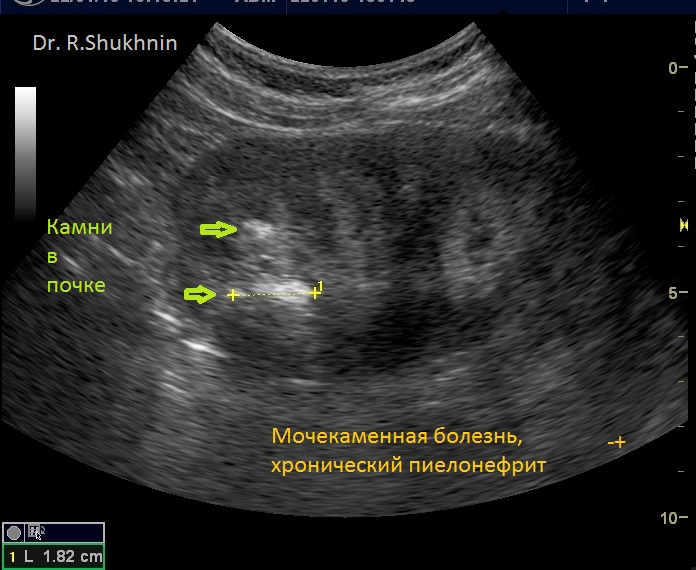

На фото из практики д-ра Шухнина Р.Е.

3) УЗИ почки. Мочекаменная болезнь: многочисленные камни почки. Заболевания почек – одна из главных причин отеков вокруг глаз.